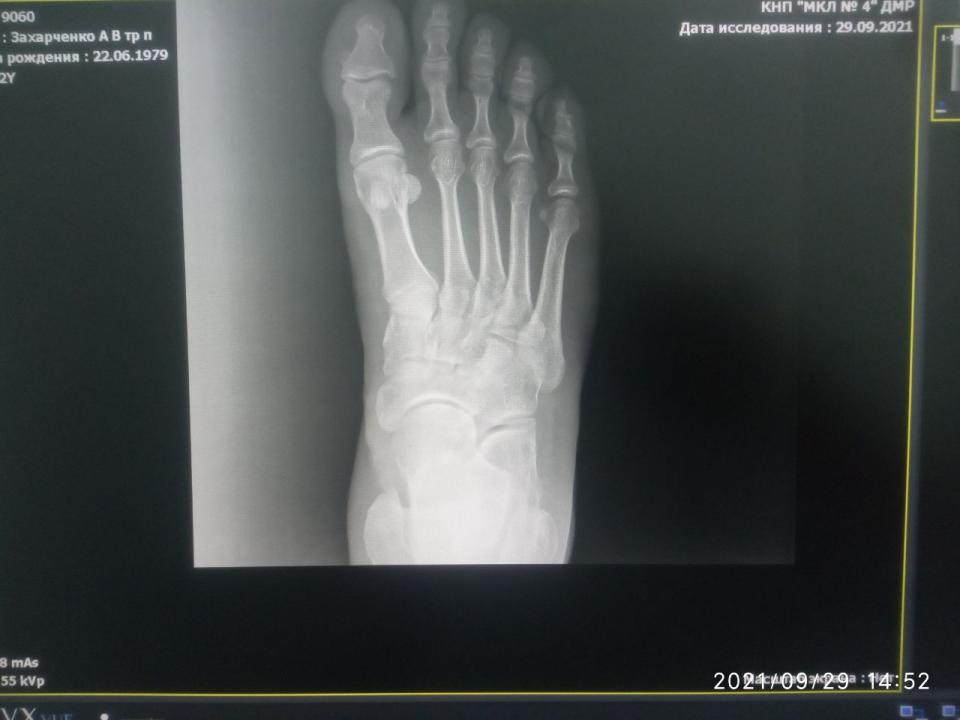

andreyyy Опубликовано 5 октября, 2021 Опубликовано 5 октября, 2021 Драсьте На фоне истощения организма, плохо заживающих ранок, падения иммунитета, что является вообще отдельной темой, не для обсуждения, я неудачно спрыгнул с брусьев. С невысоких. С собственным весом около 70 кг. Просто знаете, бывает, что не достаточно самортизировал и в стопе возникла боль при приземлении. Это было, дай бох памяти, в понедельник прошлой недели. Т.е. 8 дней назад. Сначала боль была несильная. На утро легкая, вполне себе не вызывающая беспокойства. Пошел на работу. От проходной до моего участка работы пешком далеко. Т.е. каждодневный поход н аработу - это всегда большая нагрузка в плане ходьбы. Особенно если опаздываю и иду быстрым шагом. Так я сильно мучился, когдда несколько месяцев не заживали мозоли-волдыри, нратертые обувью. Я купил эластичный бинт и перемотал стопу. По неопытности перетянул сильней необходимого. Идти стало еще больней. Шел через боль, пока боль не стала очень сильной. Остановился, размотался... К вечеру нога разболелась очень сильно. Когда говорю очень, то это буквально. Обезболился, лег спать. Проснулся утром, а боль уже невыносимая. Невозможно ступить на ногу вообще. Больно даже легонько прикоснуться пальцем к коже стопы. Я уссыкаюсь, а не могу идти. Я зову на помощь, мне несут ведро. При этом еще и морозить стало. Я измерил - 39. Напился Парацетамола, Ибупрофена, уколол 3 кубика кетанова и несколько ампул налбуфина. К последнему толерантность и он плохо действует в плане обезболивания. Зависимости нет (была), но толерантность высокая. Одна ампула вообще не дает эффекта. Как-то так. В общем, обезболился и на работу не пошел. Интенсивность боли показалась ненормальной и я поехал на такси в травмпункт. А, сначала получил направлениеп от семейной. Уже попускали лекарства, даже покачивания в такси вызывали сильную пульсирующую боль. Наступил на камушек, так заорал криком... Травмпункт отказался принимать, т.к. они работают только в первые сутки после травмы. Моя семейная такая - всю жизнь меня куда-то направляет, где говорят, что она дура и этот не к ним. Умеет только бубнеть, как сложно ей живется после реформы и как сбоит программа (просто время отклика на клик было чуть дольше чем на хорошем современном ПК, все работает четко, но она бубнит, что вот снова невозможно работать, реформа....). Короче, я там начал ругаться. Я еще нервный последнее время и на транках, которые не работают уже нихера. А шишки потерял ( Добился приема заведующего отделением. Направил на рентген. Я сфотографировал снимки на мониторе и показал ему на телефоне. Он сказал, что все пучком, все в целостности. Прописал покой, холодные компрессы, легкая намотка и капустный лист. Не шутка. А если будет болеть, немид. Если вдруг понадобится больничный, то к семейному. Вот эти "если" умиляли. Я ему же объяснил, что я несколько часов назад не мог до туалета дойти. На следующее утро та же история. В течение дня я всем чем можно обезболиваюсь, соблюдаю режим щадящий, но стоит заснуть и проснуться, как боль невыносимая и невозможно вообще даже с палочкой пройти и пару шагов. Я обнаружил, тчо кетанов не работает совсем. Вчера поставил 3 кетанова и 3 трамадола и боль ушла примерно на 60% Трамадол был последний. Оставалось на всякий случай в заначке 3 кубика. Сегодня ночью я жменями жрал пенталгин, темпалгин, ибупрофен, т.к. не хотел будить никого. Утром докупили кетанов. 2 кубика. Полнейшее отстутствие эффекта. Еще 2. Вообще ноль При этом я абсолютно уверен, что кетанов на мне работает отлично. От сильной зубной или послеоперационной боли 2 кубика снимают боль полностью. Не на долно, но полностью. Никак не связан его эффект с падением эффективности опиоидов. Я озадачен. Я не могу придумать, по какой еще причине он может не работать кроме проблем с кровообращением. С кровообращением, кстати, и правда жопа. Кончики пальцев на ногах потеряли чувтствительность. Но нога-то распухшая, кроме как кончики пальцев всюду чувствительнсоть есть. Уколол 1 налбуфин. Сижу терплаю. Дергает и пульсирует. Усомнившись в правильном ракурсе снимка, я повторно через семейного выбил направление к нашему местному травматологу. Там сделали снимог на пленку. Не знаю, как его выложить. Не могу сфотографировать, чтобы что-то было четко видно. ВЫстоял очередь к травматологу... И хорошо, что с криком "Да пошел ты " выскочил, хлопнув дверью, что штукатурка посыпалась, ибо так психанул, что если бы не выскочил, то перее..л бы его палкой (я с папиной палкой сейчас хожу), Он отказался даже смотреть снимки. К нему только по записи. По направлению нельзя. К тому же он последний день перед отпуском. Последнее он повторил несколько раз. К чему? Сейчас-то он на работе! Я стою с сильной болью, приехал на такси на одолженные деньги, а он давит лыбу и говорит, что он уже почти в отпуске и меня не примит. Ну я начал колоть диклофенак, пить Серротопептидазу. Никаких изменений. Первый рентген (цифровой) Показать Показать Показать Показать Показать Селфи Показать Селфи только что Показать Диагноз поставли "или растяжение или надрыв". Прошу совета. Я сейчас и так очень сильно погружен в решение своих других проблем и не могу много времени выделить на походы по больницам. Ждать и само заживет или что-то идет не так ? КАкие варианты ? Навскидку устрпоит. Вообще чтоб понимать, что МОЖЕТ быть. Чем обезболиваться ? Я не могу вспомнить хороший нецентрального действия преп, который тоже хорошо помогает в плане обезболивания (чуть ли не на уровне кетаролака). Что из сильного ненаркотического ? буду пробовать все.